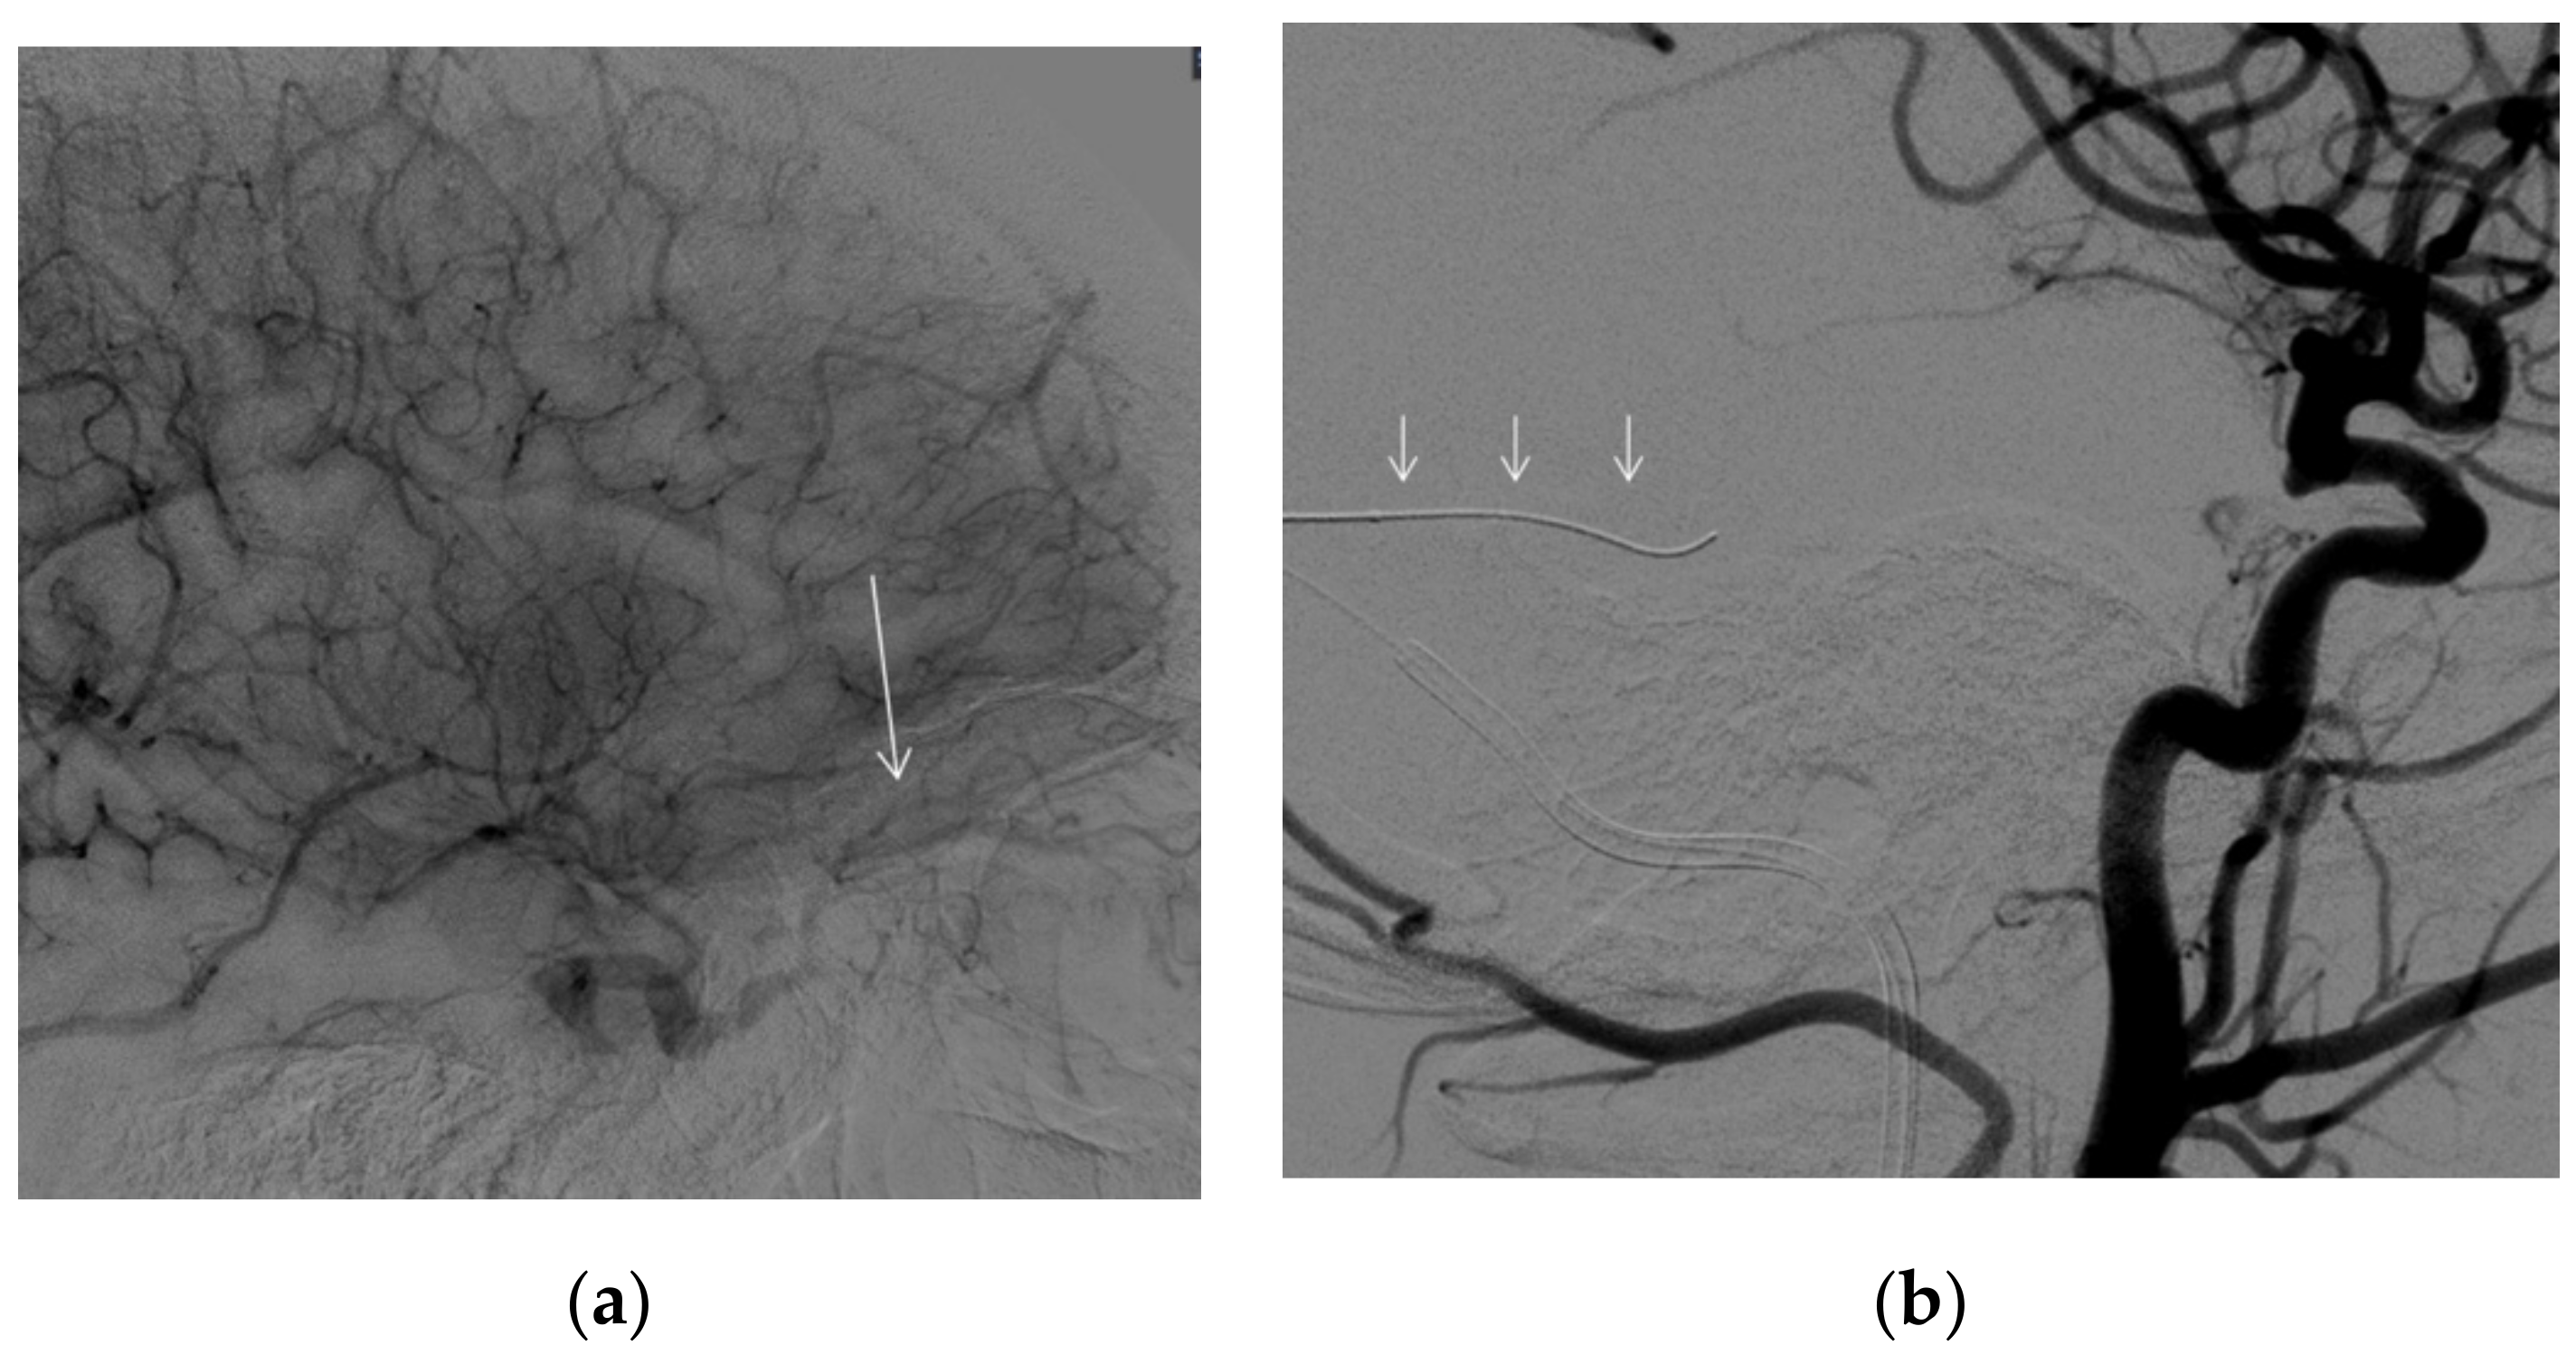

A 68-year-old female was admitted to our emergency department referring in the last two months a left retro-orbital pain associated with lacrimation and visual disturbance. Objectively, she presented redness and edema of the conjunctiva with spontaneous retrobulbar pain and pain on up or down gaze (Clinical Activity Score > 3/7). She had subjective intermittent diplopia due to eye motility impairment without signs of optic nerve involvement, such as visual acuity loss. She had two sisters affected by thyroid disease, and her personal history was significant for past smoking, hypercholesterolemia, and inflammatory bowel disease. She had also previously been diagnosed with euthyroid Hashimoto’s thyroiditis with a slight increase in antibodies to thyroid peroxidase (TPOAbs) and normal levels of antibodies to the TSH receptor (TRAbs). General and neurological examination did not show any other significant finding. The unilateral involvement, the euthyroid state, and the negligible TPOAbs and TRAbs titolation were not deemed to be related to the underlying subclinical thyroid disease and led to further investigations in order to rule out potential secondary causes of unilateral retro-orbital disease (i.e., brain or retro-orbital tumors, vascular diseases, or malformations). Orbital MR scans (Philips Ingenia CX 3T scanner. T1 [TR 539.4, TE 14] and T2 [TR 2500, TE 90] weighted sequences, with slice thickness of 3 mm, on the coronal plan, and T1 weighted [TR 446.2, TE 8.0], with slice thickness of 2.5 mm, on the axial plan. All sequences were acquired with the chemical shift-based water–fat separation Dixon method) confirmed a left exophthalmos and showed global left extrinsic ocular muscles increase in size without significant hypertrophic superior or inferior ophthalmic vein (Figure 1a,b).

Figure 1. (a) MR, T2-weighted image, coronal plane, confirming a bilateral global hypertrophy of the extrinsic muscles, more pronounced to the left superior rectus (white arrow). (b) MR, T1-weighted fat-sat postgadolinium image, axial, showing a slightly enlarged left superior ophthalmic vein (dashed arrow), partially pinched by the superior rectus muscle.